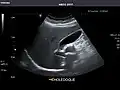

Gallbladder -

Gallbladder